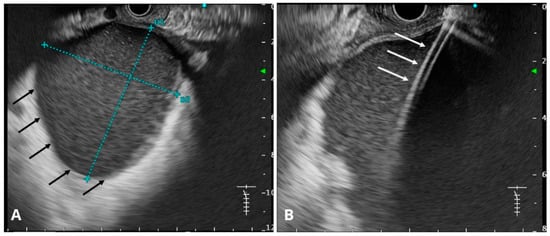

6.12. Endoscopic Ultrasound (EUS)

6.14. Transabdominal Ultrasound and CT Imaging